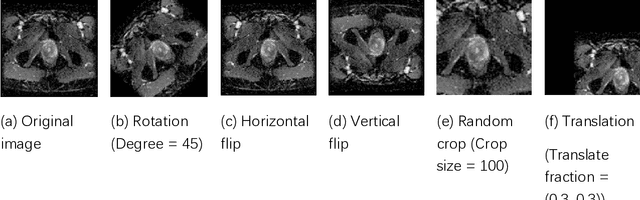

Abstract:Data augmentation refers to a group of techniques whose goal is to battle limited amount of available data to improve model generalization and push sample distribution toward the true distribution. While different augmentation strategies and their combinations have been investigated for various computer vision tasks in the context of deep learning, a specific work in the domain of medical imaging is rare and to the best of our knowledge, there has been no dedicated work on exploring the effects of various augmentation methods on the performance of deep learning models in prostate cancer detection. In this work, we have statically applied five most frequently used augmentation techniques (random rotation, horizontal flip, vertical flip, random crop, and translation) to prostate Diffusion-weighted Magnetic Resonance Imaging training dataset of 217 patients separately and evaluated the effect of each method on the accuracy of prostate cancer detection. The augmentation algorithms were applied independently to each data channel and a shallow as well as a deep Convolutional Neural Network (CNN) were trained on the five augmented sets separately. We used Area Under Receiver Operating Characteristic (ROC) curve (AUC) to evaluate the performance of the trained CNNs on a separate test set of 95 patients, using a validation set of 102 patients for finetuning. The shallow network outperformed the deep network with the best 2D slice-based AUC of 0.85 obtained by the rotation method.